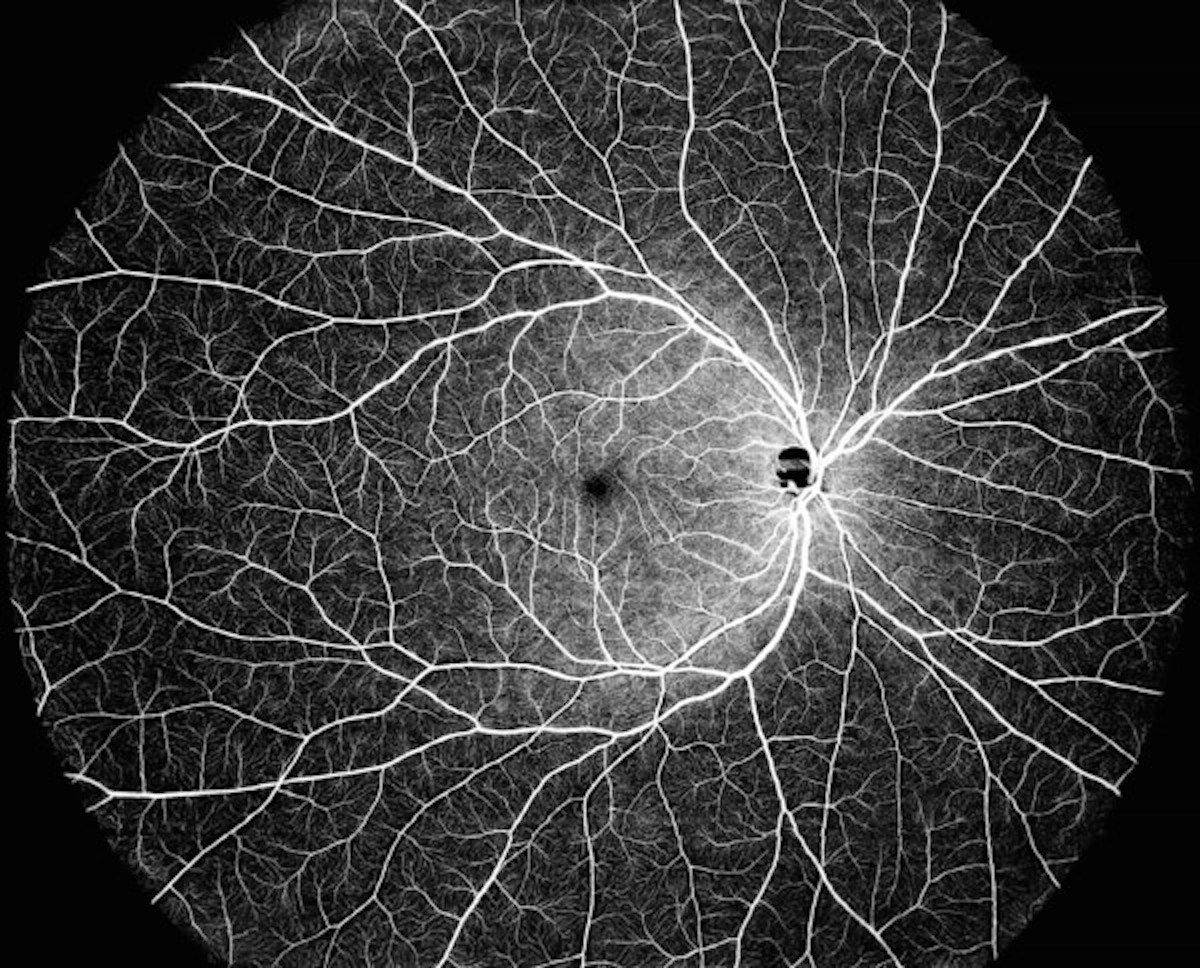

Fundus images of diabetic retinopathy were assessed by general ophthalmologists, retina specialists and the Aireen artificial intelligence system